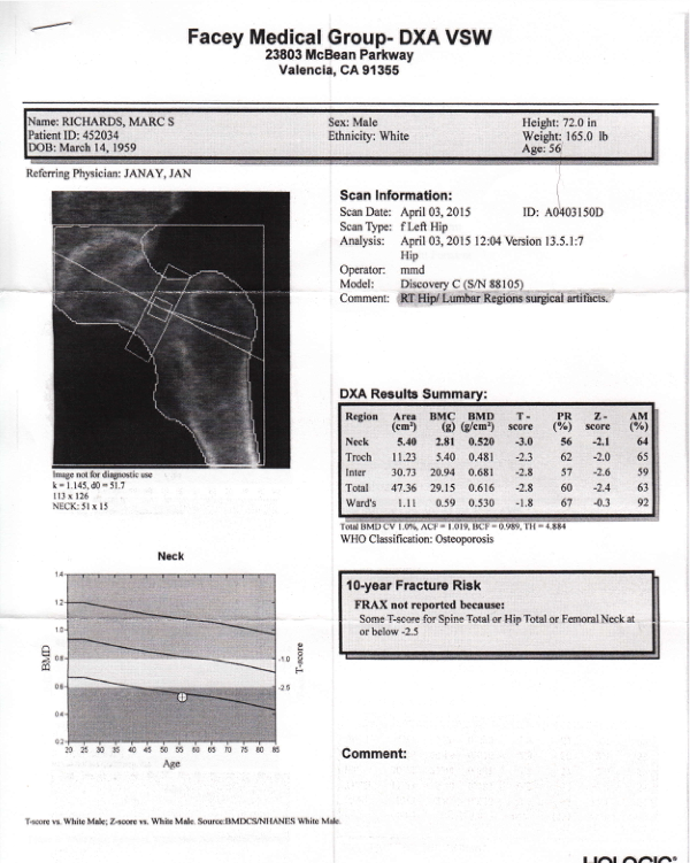

Bone Density 2015

2015:

I seems that I have slid a little backwards. This test shows a T score of -2.8.